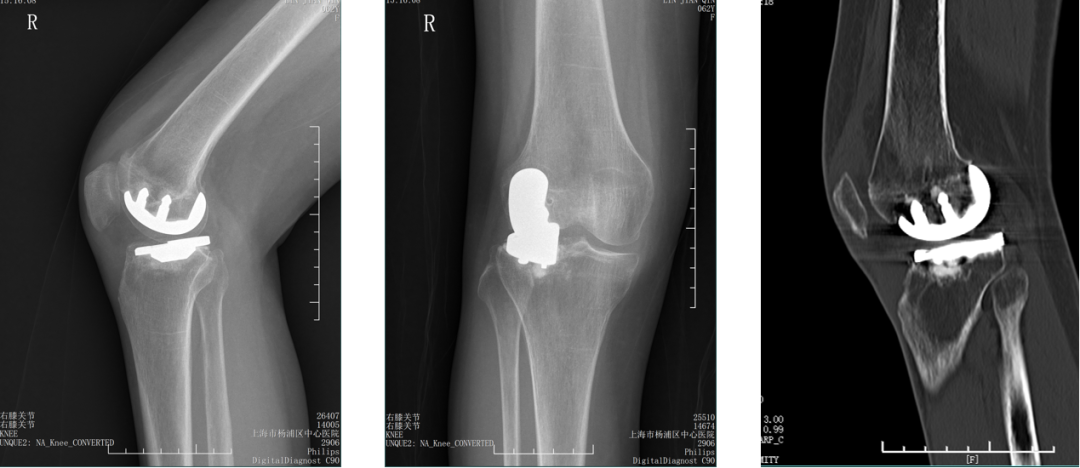

股骨后髁过截

外侧股骨髁坏死伴发育不良。

股骨假体过屈

外侧单髁术后股骨后髁过截,股骨假体过屈(45°)。